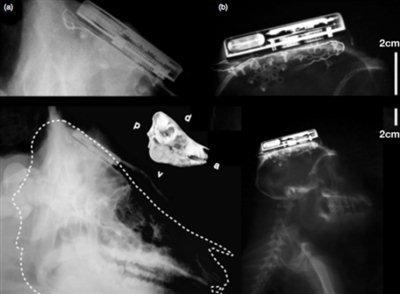

Η συσκευή έχει το μέγεθος σπιρτόκουτου και τοποθετείται στο κεφάλι του τελευταίου. Ένα μικροσκοπικό καλώδιο συνδεδεμένο με ένα chip 100 ηλεκτροδίων εκτείνεται από τη συσκευή μέχρι το κεφάλι του χρήστη και καταγράφει δεδομένα από τον εγκέφαλο του. Η αποστολή των δεδομένων στον υπολογιστή πραγματοποιείται μέσω ασύρματης κεραίας από απόσταση μέχρι και ενός μέτρου. Η συσκευή διαθέτει επαναφορτιζόμενη (μέσω ασύρματης επαγωγής) μπαταρία λιθίου 200mAh με αυτονομία 7 ωρών. Η νέα τεχνολογία έχει δοκιμαστεί επιτυχώς σε ζώα, σύμφωνα με τους ερευνητές όμως δεν είναι έτοιμη για δοκιμές στον άνθρωπο. teckgear